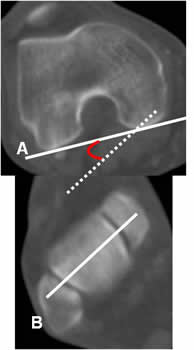

Torsión tibial:

Medido mediante TAC, con cortes axiales que se superponen. Uno sobre la tuberosidad tibial y otro en el tobillo, a nivel de la base de los maleolos. (3).

La tibia tiene una retroversión externa normal, de 15º a 20º en los adultos. (3).

El ángulo se forma por la línea tangente a la epífisis tibial posterior y el eje bimaleolar del tobillo. Su valor promedio es de 35º. (18, 22). (Fig 80 y 81).

Fig 80. Torsión tibial.

A: TAC axial a nivel de la espina tibial y línea que pasa por la parte posterior de la tibia.

B: TAC axial, con línea sobre el eje bimaleolar del tobillo.

Se superponen y forman el ángulo de torsión tibial.

Angulo cóndilo-maleolar:

Medido mediante TAC, con cortes axiales que se superponen. Uno sobre los cóndilos femorales y otro en el tobillo, a nivel de la base de los maleolos. (3).

El ángulo se forma por las líneas bicondilea posterior y el eje bimaleolar del tobillo. Su valor promedio es de 39º. (3). (Fig 82 y 83).

Fig 82. Angulo cóndilo-maleolar.

A: TAC axial, con línea que pasa por la parte posterior de los cóndilos femorales.

Se superponen y forman el ángulo cóndilo-mandibular.